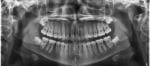

Ortodonția modernă oferă astăzi mai multe opțiuni ca oricând pentru a obține un zâmbet perfect. De la aparatul dentar clasic, cu brackeți metalici, până la gutierele ortodontice transparente, tratamentele au evoluat pentru a combina eficiența medicală cu estetica.

Dar care este cea mai bună alegere pentru tine? În continuare comparăm cele două metode, cu toate avantajele și limitările lor, pentru ca tu să poți decide informat – împreună cu medicul ortodont.